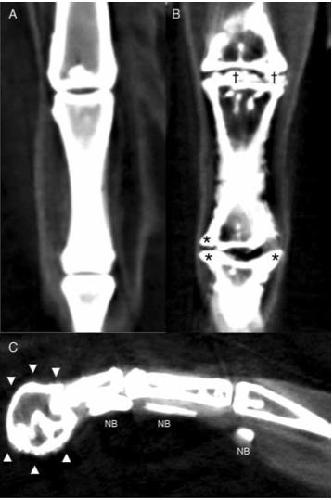

Degenerative Osteoarthropathy in Laboratory Housed Xenopus (Silurana) tropicalis., Zhang M, Wilson SS, Casey KM, Thomson PE, Zlatow AL, Langlois VS, Green SL., Comp Med. December 1, 2021; 71 (6): 512-520.

Axial Skeletal Malformations in Genetically Modified Xenopus laevis and Xenopus tropicalis., Zlatow AL, Wilson SS, Bouley DM, Tetens-Woodring J, Buchholz DR, Green SL., Comp Med. December 1, 2020; 70 (6): 532-541.